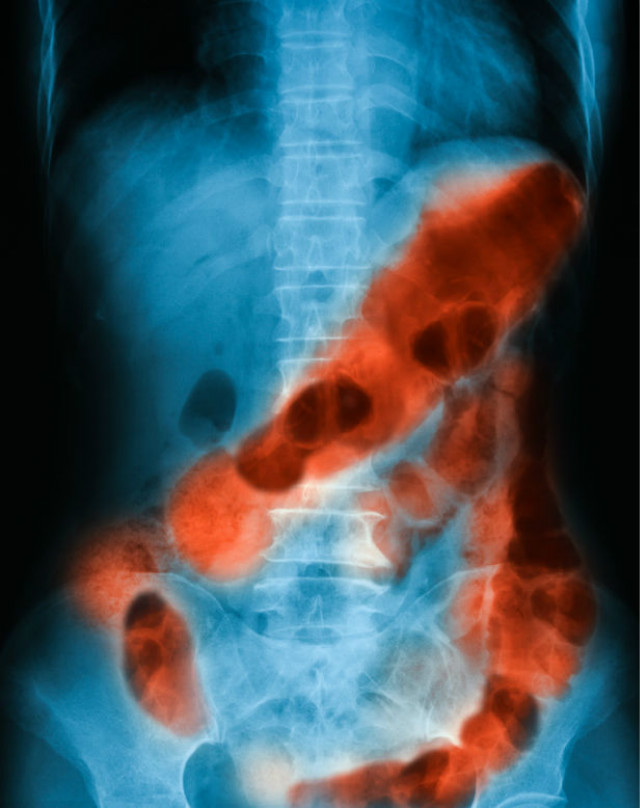

一小块生金有可能引发中毒,也有可能让尤二姐的消化道遍体鳞伤。事实上,不光是金子,吞食任何坚硬的物品,都有可能导致消化道大出血,在吞食的过程中,还可能会引发窒息。

不难想象,尤二姐硬生生吞下了生金,当出血量在400ml以下时,她的身体不会有明显的症状。可一旦引发大量出血时,就会出现头晕、心慌、冷汗、晕厥、休克等症状。随着出血量的增加,她可能发生呕血的现象,身体周围循环衰竭会导致她慢慢死亡。

由此可见,无论是中毒,还是金块导致的消化道大出血,都会让尤二姐的求死之路变得异常艰难。虽然《红楼梦》中没有详细记载,但不难想象,尤二姐死后的场面一定不像她想象的那么干净。